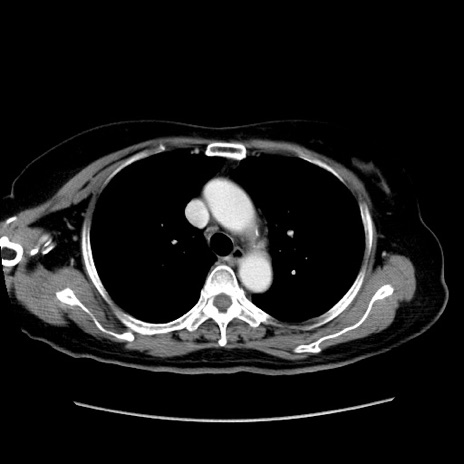

症例19(横断像)

【症例】80歳代女性

【主訴】下腹部痛

【現病歴】約8時間前より下腹部痛の出現あり、救急外来受診。

【既往歴】両側付属器切除

【身体所見】意識清明、下腹部正中に手術痕あり、その部位に一致して圧痛と反跳痛あり。腸蠕動音は亢進。

【データ】WBC 9300、CRP 0.15